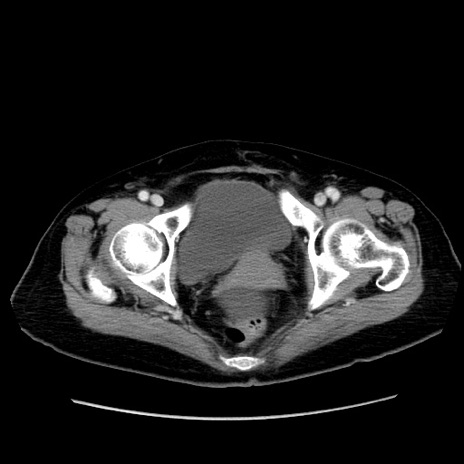

冠状断像

症例19(横断像)

【症例】80歳代女性

【主訴】下腹部痛

【現病歴】約8時間前より下腹部痛の出現あり、救急外来受診。

【既往歴】両側付属器切除

【身体所見】意識清明、下腹部正中に手術痕あり、その部位に一致して圧痛と反跳痛あり。腸蠕動音は亢進。

【データ】WBC 9300、CRP 0.15